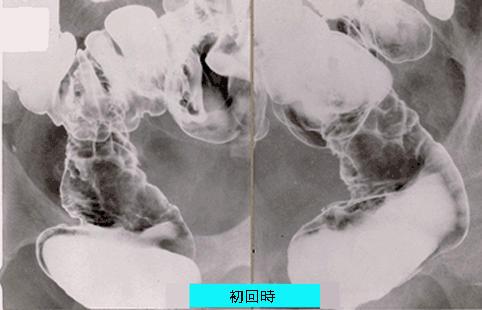

症例提示(所在地,施設名等): 東京都・ 国立がんセンター中央病院と九州がんセンターの共同作成

症例登録日 1999/01/01

画像ID:949

疾患(病理主体)の分類炎症性・潰瘍性疾患/その他

部位(臓器別)大腸/直腸

検査方法X-P

病変の最大径(ミリ)40以上